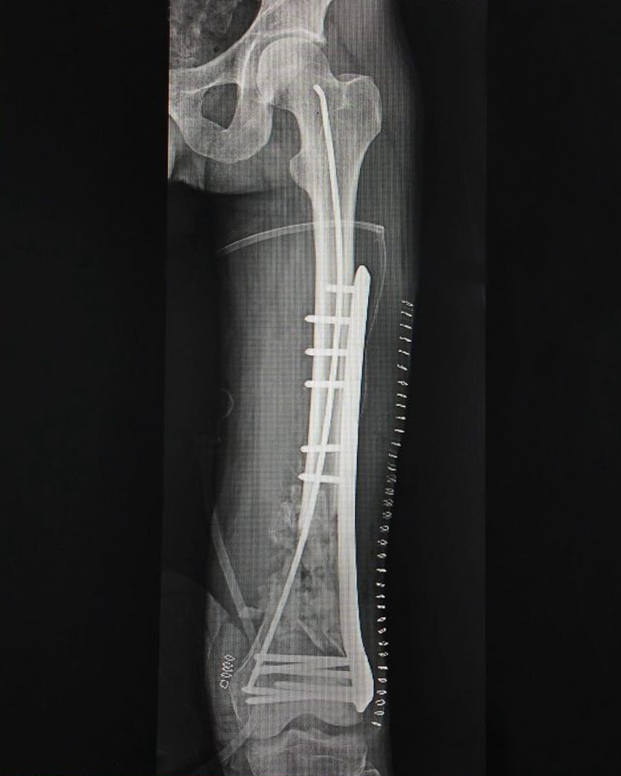

- Fracture Treatment: We specialize in the surgical and non-surgical treatment of

fractures, utilizing advanced techniques to ensure optimal healing and recovery.

- Expertise in Trauma Care: Dr. Zambare is highly skilled in managing complex trauma

cases, including multi-limb injuries and severe fractures. His expertise ensures that patients receive

precise and effective treatment for their injuries.